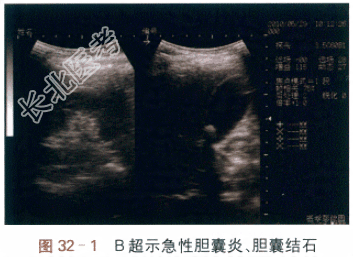

- [材料题] 患者,女性,65岁,因“右上腹痛3d,伴发热”来院急诊。患者入院前3天,进食油腻食物后,出现右上腹疼痛,呈绞痛样,间歇性加剧,向右肩背部放射,伴恶心呕吐,当天出现发热,体温最高达38.5℃,无畏寒,也无皮肤巩膜黄染。发病以来,患者无食欲、睡眠质量较差、大小便尚正常,体重无明显变化。患者5年前体检时发现胆囊结石,既往进食油腻食物后偶感右上腹胀痛不适,无明显急性发作史。糖尿病史10年,口服药物控制血糖,空腹血糖控制良好;无手术外伤史。体格检查的结果是患者神清,精神萎靡,浅表淋巴结未及明显肿大,皮肤巩膜无黄染,全腹略膨隆,右上腹明显压痛,伴反跳痛,轻度肌卫,Murphy征(墨菲氏征)阳性,肝区叩击痛阳性,肠鸣音减弱。实验室和影像学检查的结果是(1)血常规:WBC为20.85×10⁹/L,中性粒细胞比例为92%。(2)B超检查:肝周见少量积液,胆囊大小约120mm×45mm,胆囊颈部见团块状强回声,直径约25mm,胆囊壁呈双层改变,局部可见密度降低。CBD直径约5mm,下端显示不清(见图32-1)。